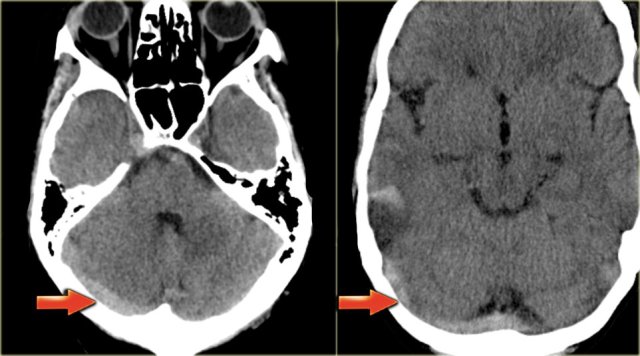

Venous infarcts (3) - vein of Labbe

Another typical venous infarction is due to thrombosis of the vein of Labbe.

On the left images demonstrating hypodensity in the white matter and less pronounced in the gray matter of the left temporal lobe.

There is a broad differential diagnosis including arterial infarction, infection, tumor etc.

Notice that there is some linear density within the infarcted area.

This is due to hemorrhage.

In the differential diagnosis we also should include a venous infarct in the territory of the vein of Labbe.

The subtle density in the area of the left transverse sinus (arrow) is the key to the diagnosis.

This is a direct sign of thrombosis and the next step is a CECT, which confirmed the diagnosis (not shown).

On the left images of a patient with hemorrhage in the temporal lobe.

When the hemorrhagic component of the infarction is large, it may look like any other intracerebral hematoma with surrounding vasogenic edema.

The clue to the diagnosis in this case is seen on the contrast enhanced image, which nicely demonstrates the filling defect in the sigmoid sinus (blue arrow).

On the left a similar case on MR.

There is a combination of vasogenic edema (red arrow), cytotoxic edema and hemorrhage (blue arrow).

These findings and the location in the temporal lobe, should make you think of venous infarction due to thrombosis of the vein of Labbe.

The next examination should be a contrast enhanced MR or CT to prove the diagnosis.